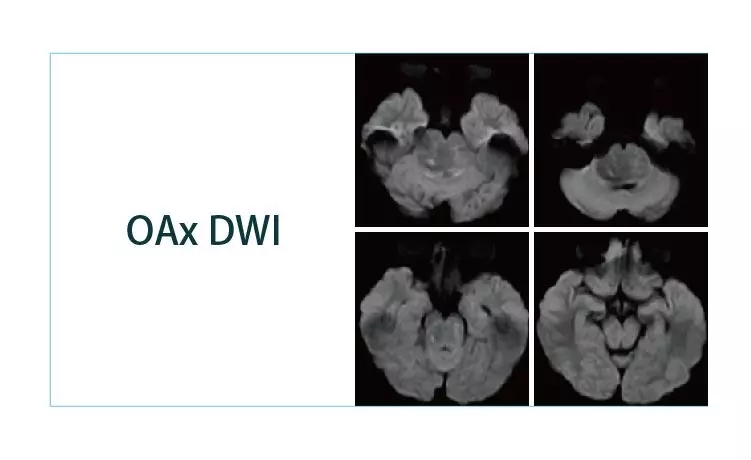

【朗润影像档案】磁共振影像病例分享(编号20190329)